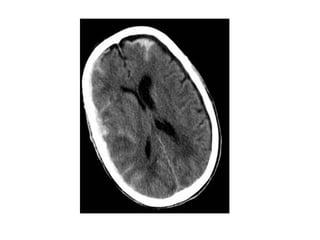

1-Normal :

-Initial appearances often normal in first few

hours , larger infarcts more prominent